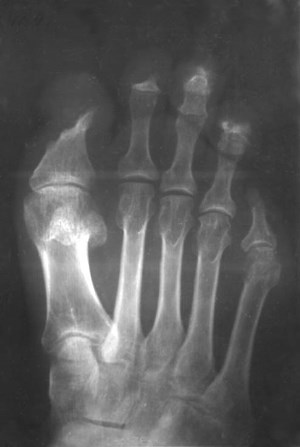

Основной способ поставить диагноз – рентген, анализ крови, КТ, МРТ.

На снимке кость не имеет четких границ.